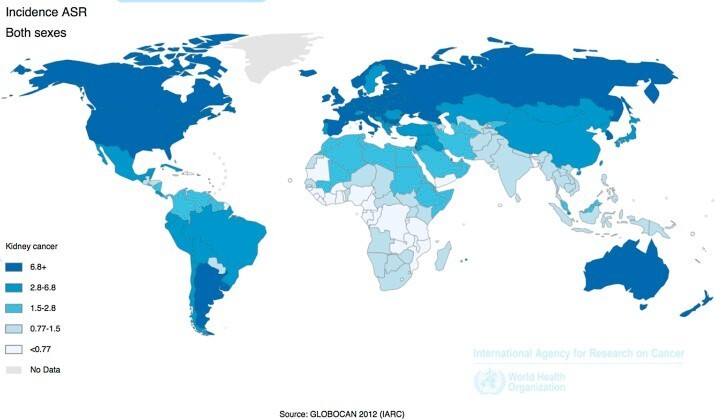

- Υψηλή επίπτωση σε Ευρώπη, Βόρεια Αμερική και Αυστραλία, ενώ

- Χαμηλή σε Ινδία, Ιαπωνία, Κίνα και Αφρική, όπως και θνητότητα (γενικότερα σε Ασιάτες και Αφρικανούς)

- 10ος πιο κοινός καρκίνος στην Ευρώπη

- 6ος σε συχνότητα καρκίνος σε άνδρες και 9ο στις γυναίκες στη Βρετανία

- Από 2007-2030 υπολογίζεται αύξηση στην επίπτωση καρκίνου νεφρού 27% και 18% σε άνδρες και γυναίκες, αντίστοιχα